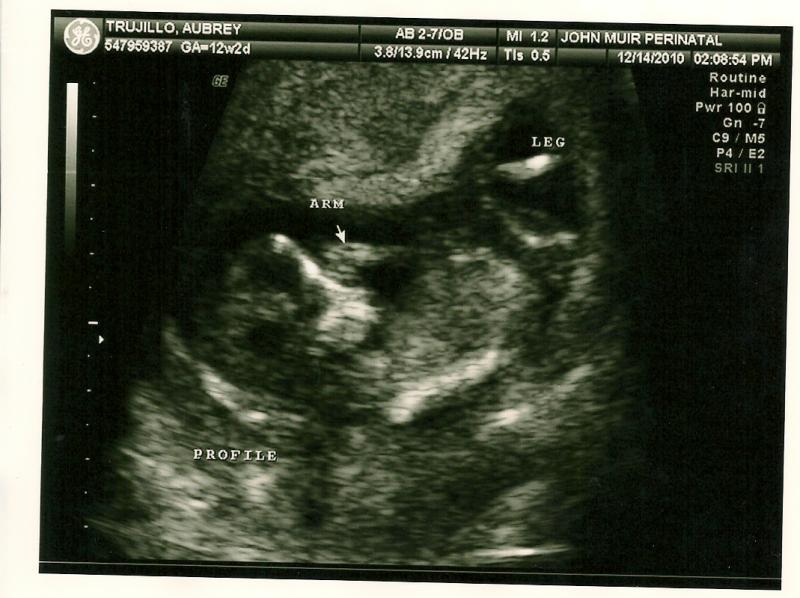

We got to see our little one's heartbeat that day!  This is all starting to feel so real....12 weeks, 2 days

We heard the heartbeat that day! 164 bpm!!!

Baby looks like Matthew, I think... but it could just be the bald head that's making me think that!  It was moving around a lot and I swear it waved at us :)12 weeks